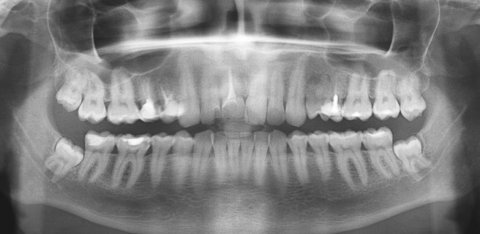

Семь лет назад лечил зуб, сделали хорошую пломбу, которая до сих пор держится, но на десне этой пломбы, два месяца назад, появился прыщик. Потом он превращался в шишку и со временем исчезал, и так много раз. Был сегодня у стоматолога в местной поликлинике, посмотрев снимки, сказала или удаляем, или оставляем. Если будет болеть, то приходи на удаление.

У вас обострение периодонтита (хроническое воспаление), дальше будет именно хуже, вплоть до удаления данного зуба. Необходимо обратиться к врачу, данная проблема лечится в несколько посещений и при неблагоприятном исходе, может затянуться на несколько месяцев.